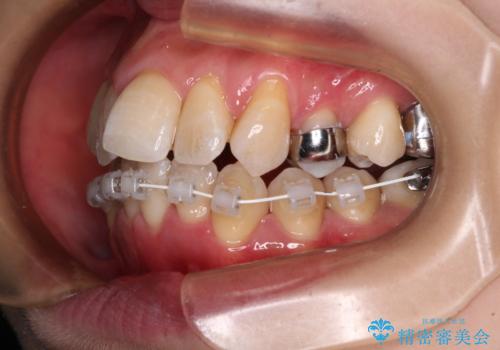

2. 治療途中

2. 【モニター】急速拡大装置 狭い歯列を拡大してワイヤー装置で短期間治療の治療中

2.